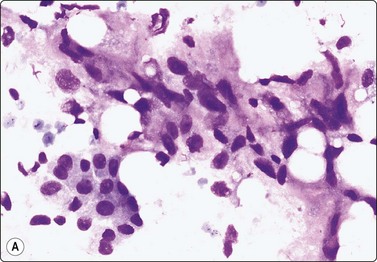

Fig. 7.2 Non-neoplastic glandular breast tissue and low-grade duct carcinoma

Low-power view; (A) Bimodal population of epithelial sheets and single bipolar nuclei of non-neoplastic glandular breast tissue; (B) Single population of epithelial cells in low-grade carcinoma (MGG, LP).

image image

Fig. 7.3 Non-neoplastic glandular breast tissue and low-grade duct carcinoma

High-power view, air-dried smears; (A) Non-neoplastic glandular breast tissue; (B) Low-grade duct carcinoma. Note single bipolar nuclei in A, and absence of bipolar nuclei, relatively mild nuclear atypia and some loss of cohesion of malignant cells in B (MGG, HP).

Fig. 7.4 Non-neoplastic glandular breast tissue and low-grade duct carcinoma

High-power view, Pap-stained smears; (A) Bimodal population in smear from non-neoplastic breast; (B) Single and clustered cells in low-grade carcinoma; some single cells probably stromal (Pap, HP).

A comparison between the basic benign pattern (non-neoplastic glandular tissue) and the most common malignant pattern (low-grade carcinoma of no special type) in FNB of breast lesions is given in Table 7.2 (Figs 7.2-7.4).

Non-neoplastic breast tissue (Figs 7.2A, 7.3A and 7.4A) Low-grade carcinoma NOS (Figs 7.2B, 7.3B and 7.4B)

1. Overall low cell yield 1. Variable but higher cell yield

2. Sheets and aggregates of cohesive, small, uniform cells 2. Irregular clusters of less cohesive, small, mildly irregular cells

3. Small rounded nuclei, bland chromatin, some overlapping 3. Slightly larger and darker nuclei, relatively bland chromatin

4. Myoepithelial cell nuclei among epithelial cells 4. Myoepithelial cell nuclei not seen

5. Variable numbers of single, bare, bipolar nuclei scattered in the background 5. Single cells, most with some cytoplasm, identical to those forming clusters; no bare bipolar nuclei